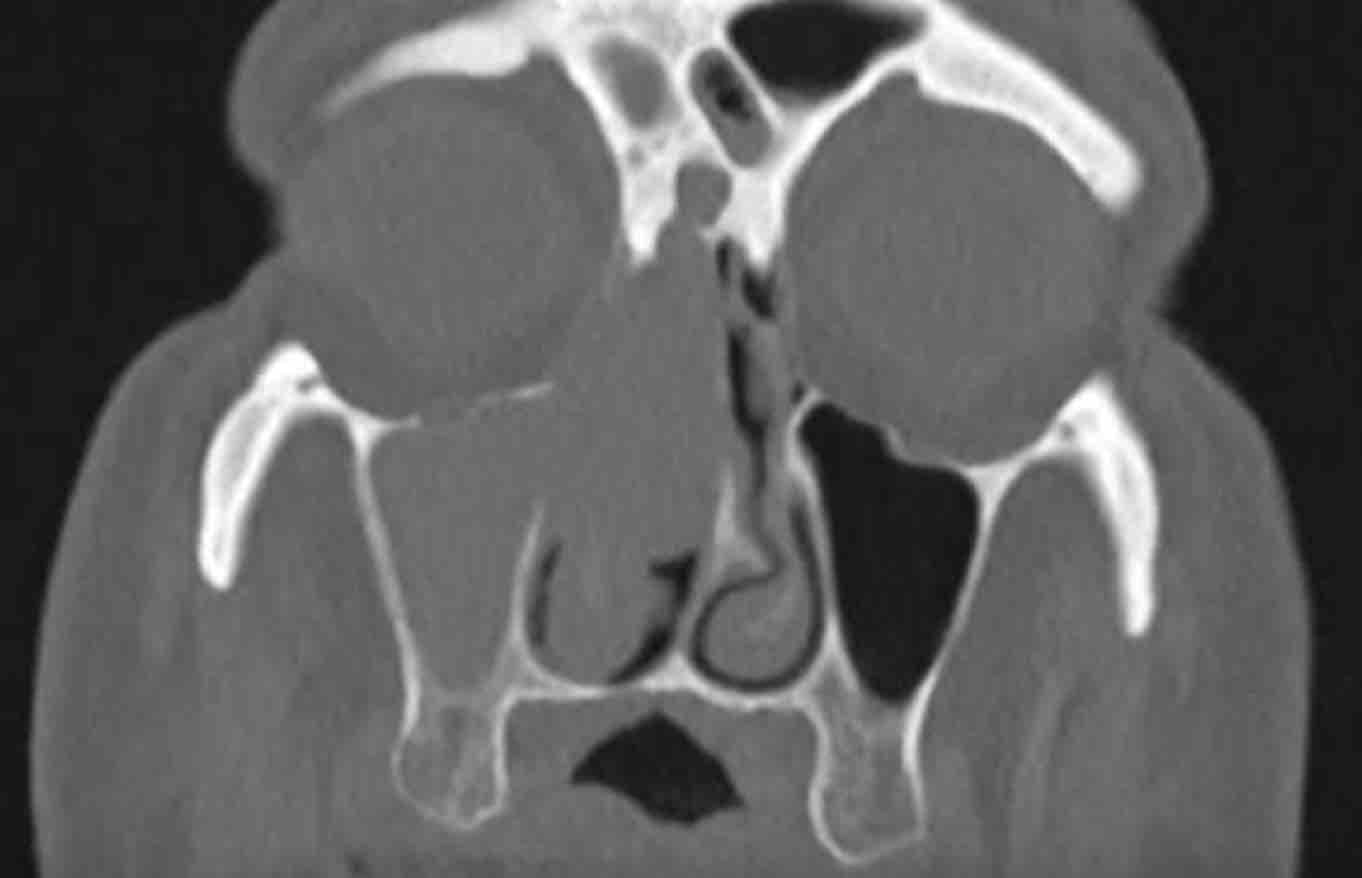

Đây là bệnh nhân có triệu chứng nghẹt mũi tắc nghẽn.

Nếu chỉ mô tả ca này đơn thuần là hình ảnh mờ gần hoàn toàn các xoang cạnh mũi bên phải, bác sĩ lâm sàng có thể dễ dàng nghĩ đây chỉ là một trường hợp viêm xoang thông thường.

Như đã đề cập, dấu hiệu cảnh báo ở đây chính là vị trí định khu bất thường một bên.

Viêm xoang một bên là cực kỳ hiếm gặp.

Hơn nữa, nếu quan sát kỹ, có thể thấy hình ảnh phá hủy vách ngăn mũi — đây là dấu hiệu cảnh báo thứ hai.